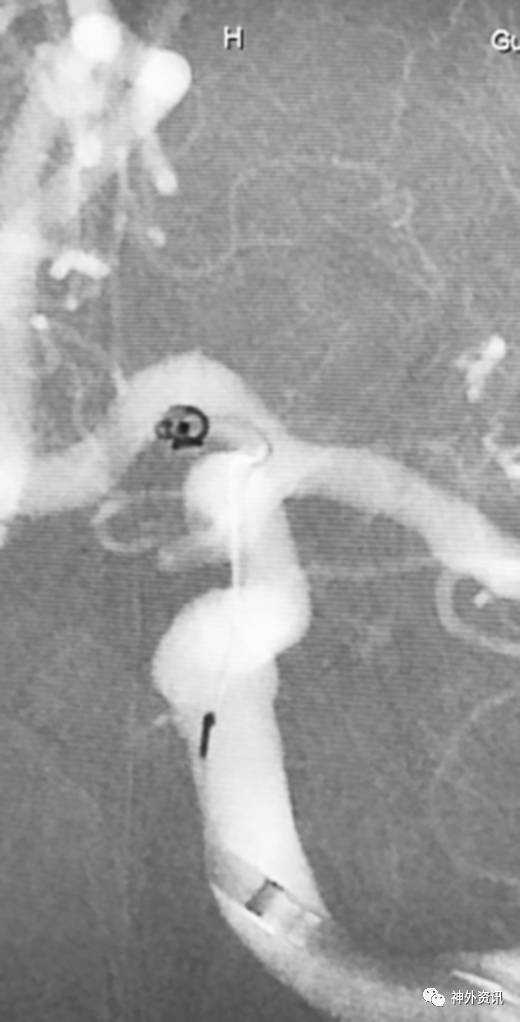

病例四

海绵窦区硬脑膜动静脉瘘,海绵窦下外侧干超选栓塞